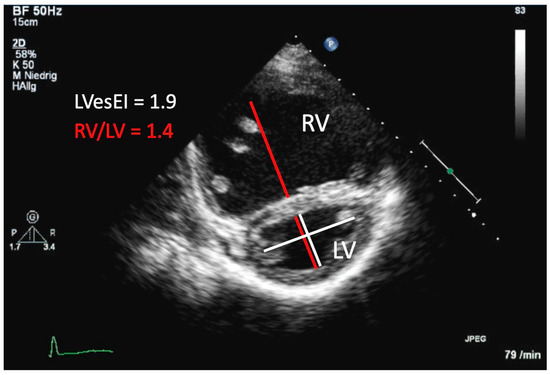

- Koestenberger, M.; Sallmon, H.; Avian, A.; Cantinotti, M.; Gamillscheg, A.; Kurath-Koller, S.; Schweintzger, S.; Hansmann, G. Ventricular-ventricular interaction variables correlate with surrogate variables of clinical outcome in children with pulmonary hypertension. Pulm. Circ. 2019, 9. [Google Scholar] [CrossRef]

- Jone, P.-N.; Hinzman, J.; Wagner, B.D.; Ivy, D.D.; Younoszai, A. Right Ventricular to Left Ventricular Diameter Ratio at End-Systole in Evaluating Outcomes in Children with Pulmonary Hypertension. J. Am. Soc. Echocardiogr. 2014, 27, 172–178. [Google Scholar] [CrossRef]

| RV/LV ratio | Reflects extent of LV compression; Ratio > 1—PH is likely; | Cannot be used in PH patients with significant left-to-right shunt lesions; Other causes of IVS flattening must be excluded (e.g., RVOTO, PS, PR) Structure and shape of IVS may be altered postoperative (e.g., VSD Patch); Not applicable in patients with single ventricle |

| LVEI | Reflects extent of LV compression; Index > 1.7 indicates adverse outcome in adult PH | |

| LVpsEIM | Reflects maximal extent of LV compression; Significantly increased in pediatric PH | |